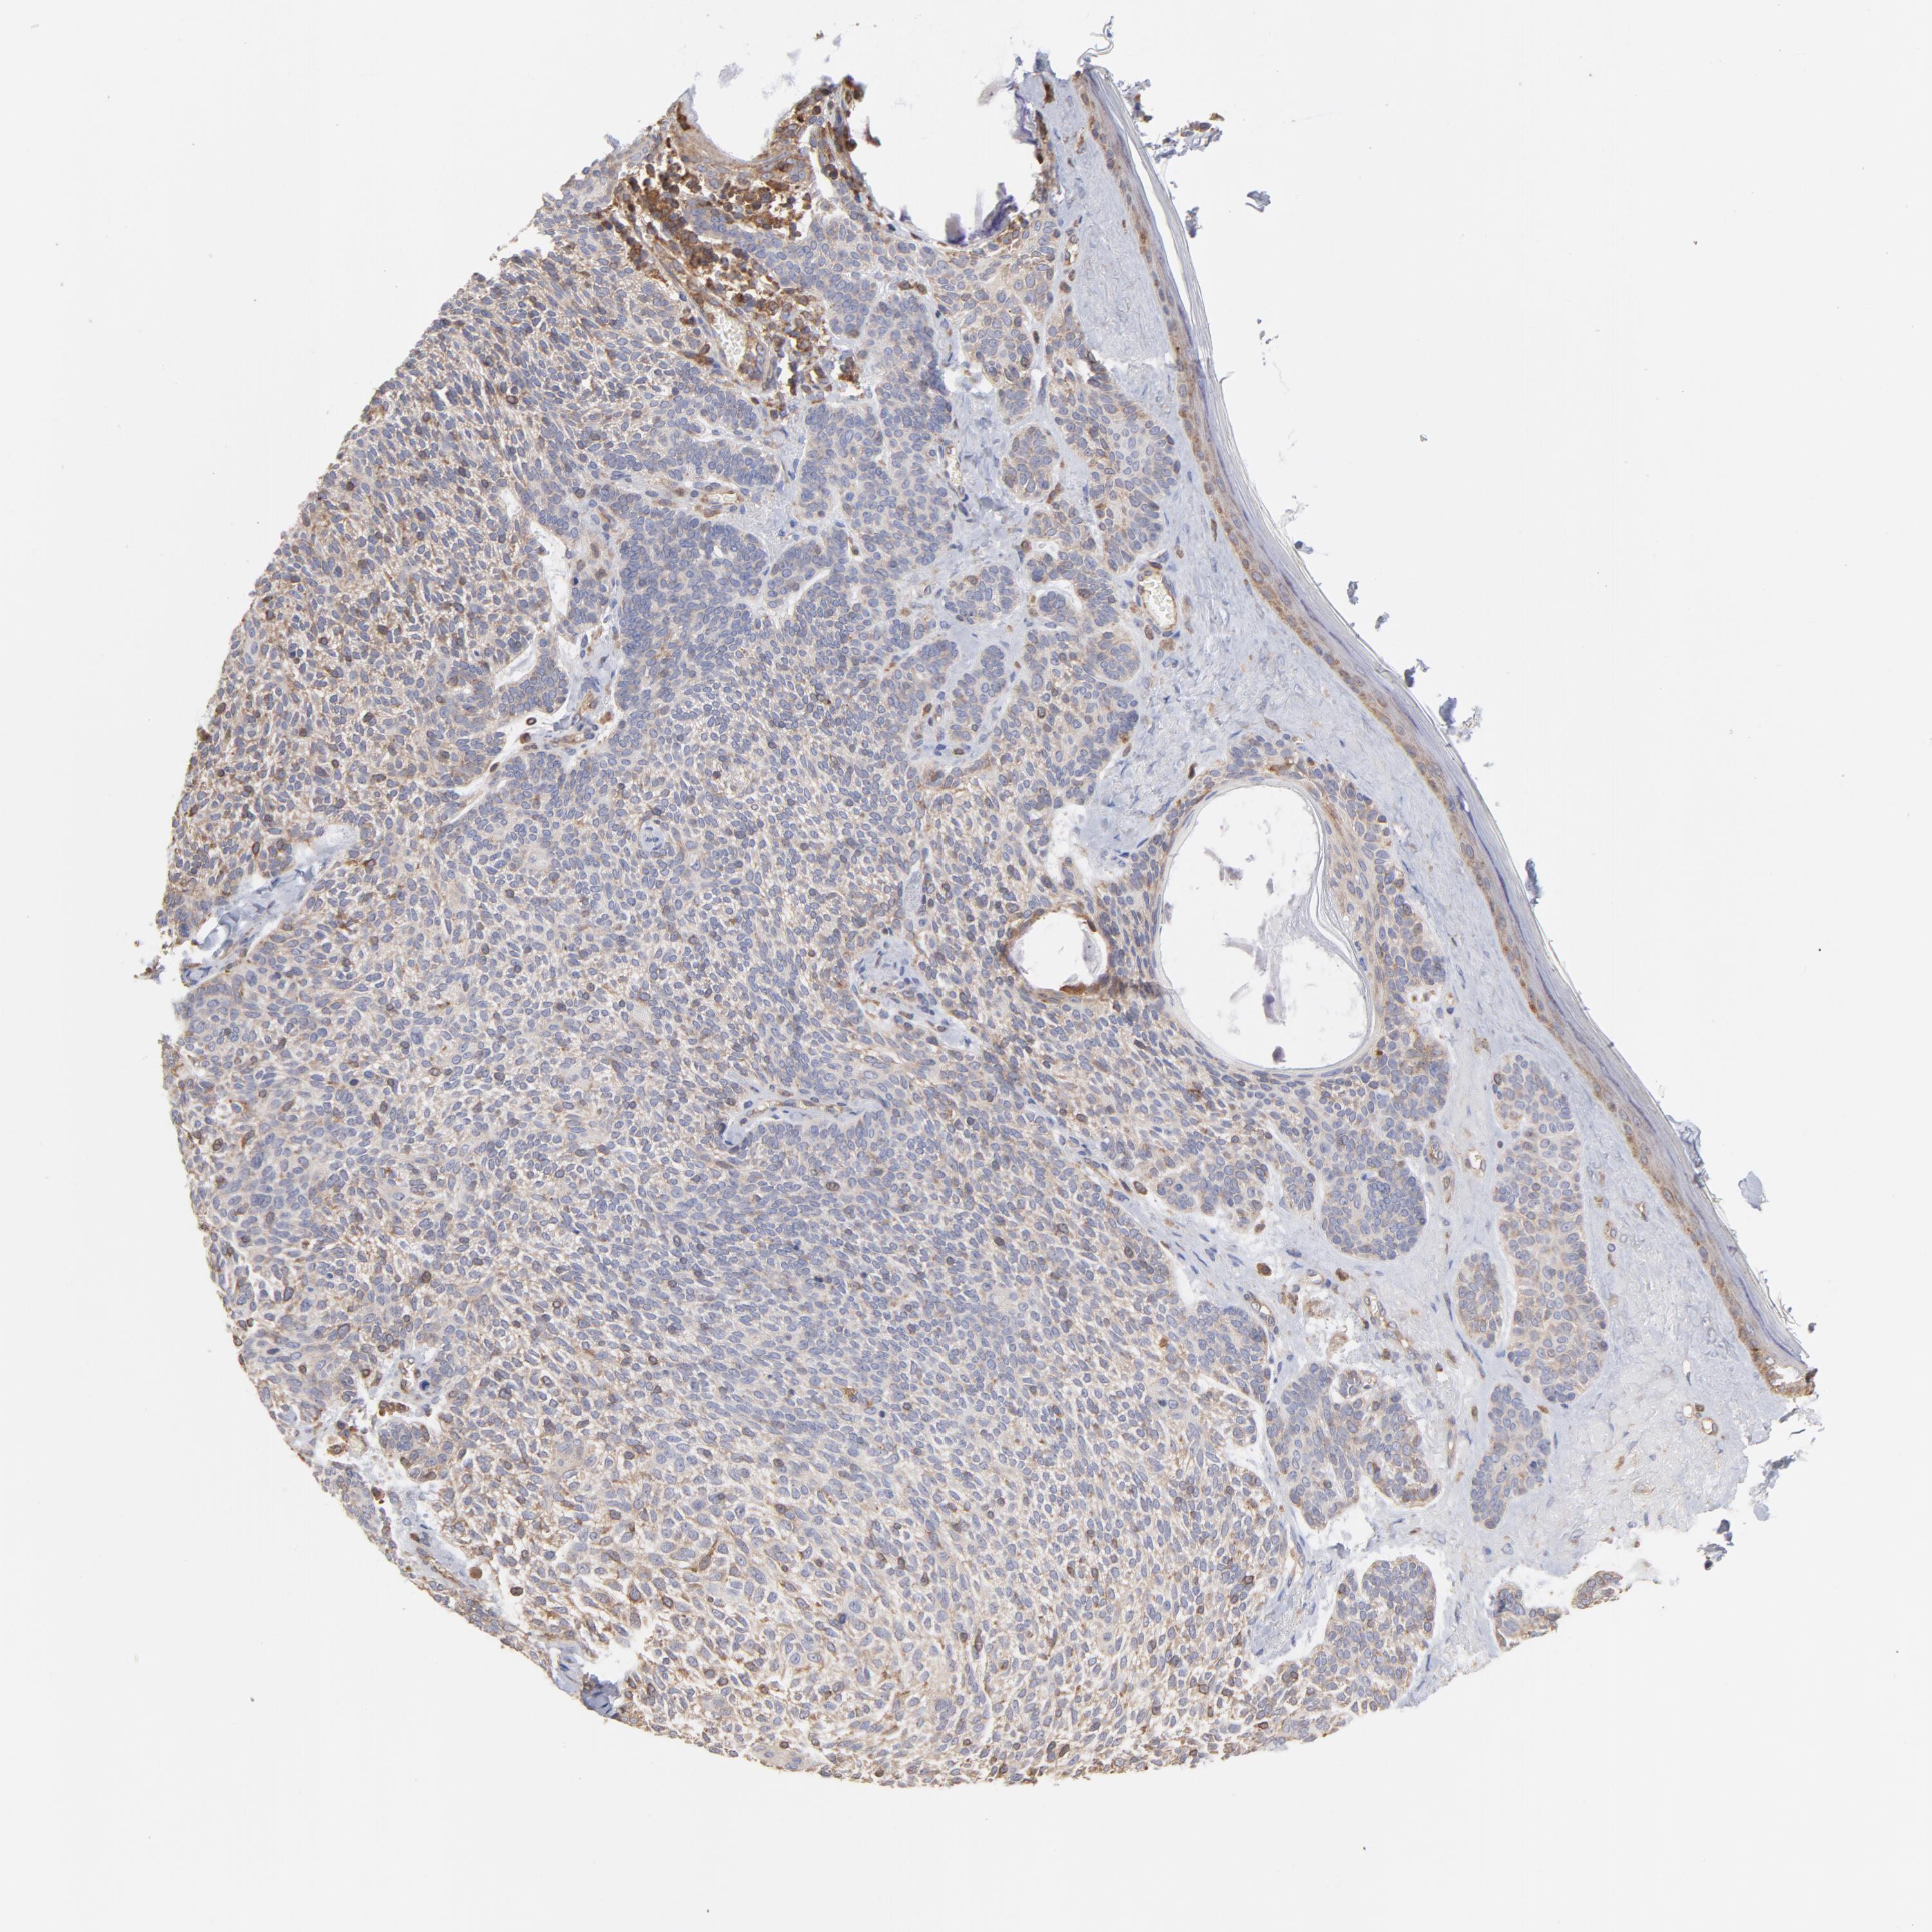

SKIN CANCER - Protein expressioni

A mouse-over function shows sample information and annotation data. Click on an image to view it in a full screen mode. Samples can be filtered based on level of antibody staining by selecting one or several of the following categories: high, medium, low and not detected. The assay and annotation is described here.

Antibody stainingi

Antibody staining in the annotated cell types in the current human tissue is reported as not detected, low, medium, or high, based on conventional immunohistochemistry profiling in selected tissues. This score is based on the combination of the staining intensity and fraction of stained cells.

Each image is clickable and will lead to virtual microscopy that enables deeper exploration of all samples and also displays staining intensity scores, fraction scores and subcellular localization as well as patient and tissue information for each sample.

Antibody CAB009337

Basal cell carcinoma